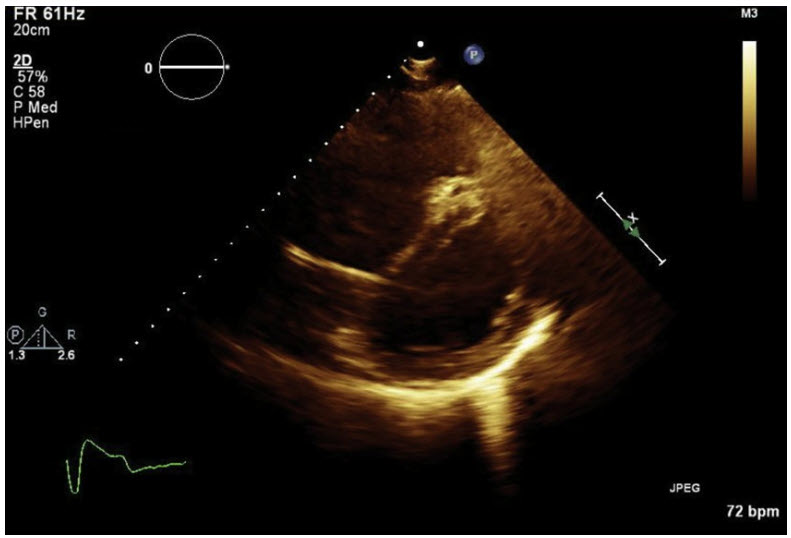

A 54-year-old woman with a history of mechanical mitral valve replacement for endocarditis is brought to the emergency department for dyspnea. She reports 2 weeks of progressive fatigue, exertional dyspnea, and orthopnea. A CT angiogram of the chest shows diffuse ground-glass opacities and interstitial thickening and is negative for pulmonary embolism. A bedside cardiac ultrasound is performed, and the parasternal short axis view is shown in the figure tbelow.

Which of the following assessments will likely lead to the diagnosis in this case?

A. Doppler ultrasound of the lower extremity veins

B. Color Doppler of the main pulmonary artery

C. Measurement of the IVC diameter in a subcostal view

D. Continuous-wave Doppler across the mitral valve in the apical 4- chamber view